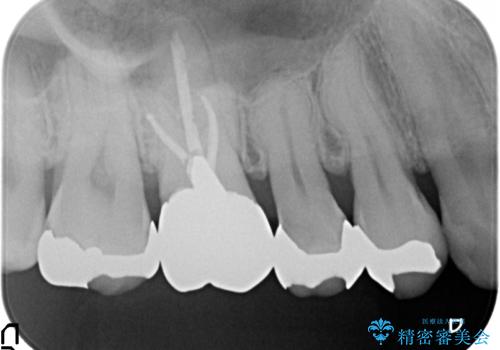

- 右上5番目の歯がなにもしなくてもズキズキ痛むので診て欲しいといらっしゃった方の症例です。

診査の結果神経を保存するのは困難だったため、根管治療を行った後、オールセラミッククラウンによる補綴を行いました。